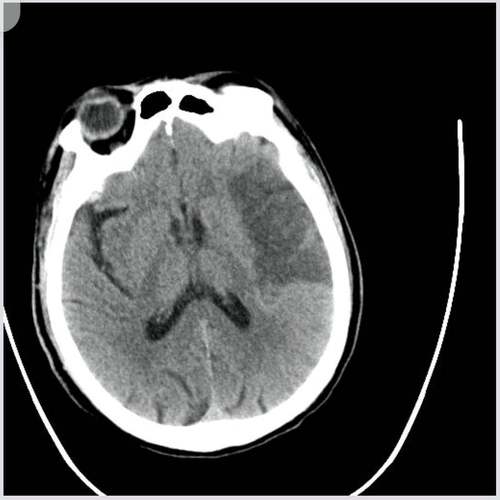

患者有脑梗死的症状和体征,但头颅CT检查没有显示出脑梗死的典型改变。

这并不排除脑梗死的诊断,反而高度提示超早期脑梗死,CT在发病后的几个小时内对脑梗死的敏感性不高,这是正常现象。

头颅CT主要是通过看脑组织的密度变化来发现问题的,脑梗死的发生和发展有其时间规律,而CT影像上的异常变化会滞后于这个时间过程。

- 发病6小时内(超早期):这是脑梗死治疗的“黄金时间窗”,在这个阶段,脑细胞刚刚开始缺血缺氧,细胞水肿非常轻微,CT上几乎看不到任何密度改变,即使已经发生了血管堵塞,CT报告也可能完全正常。这是最常见的情况。